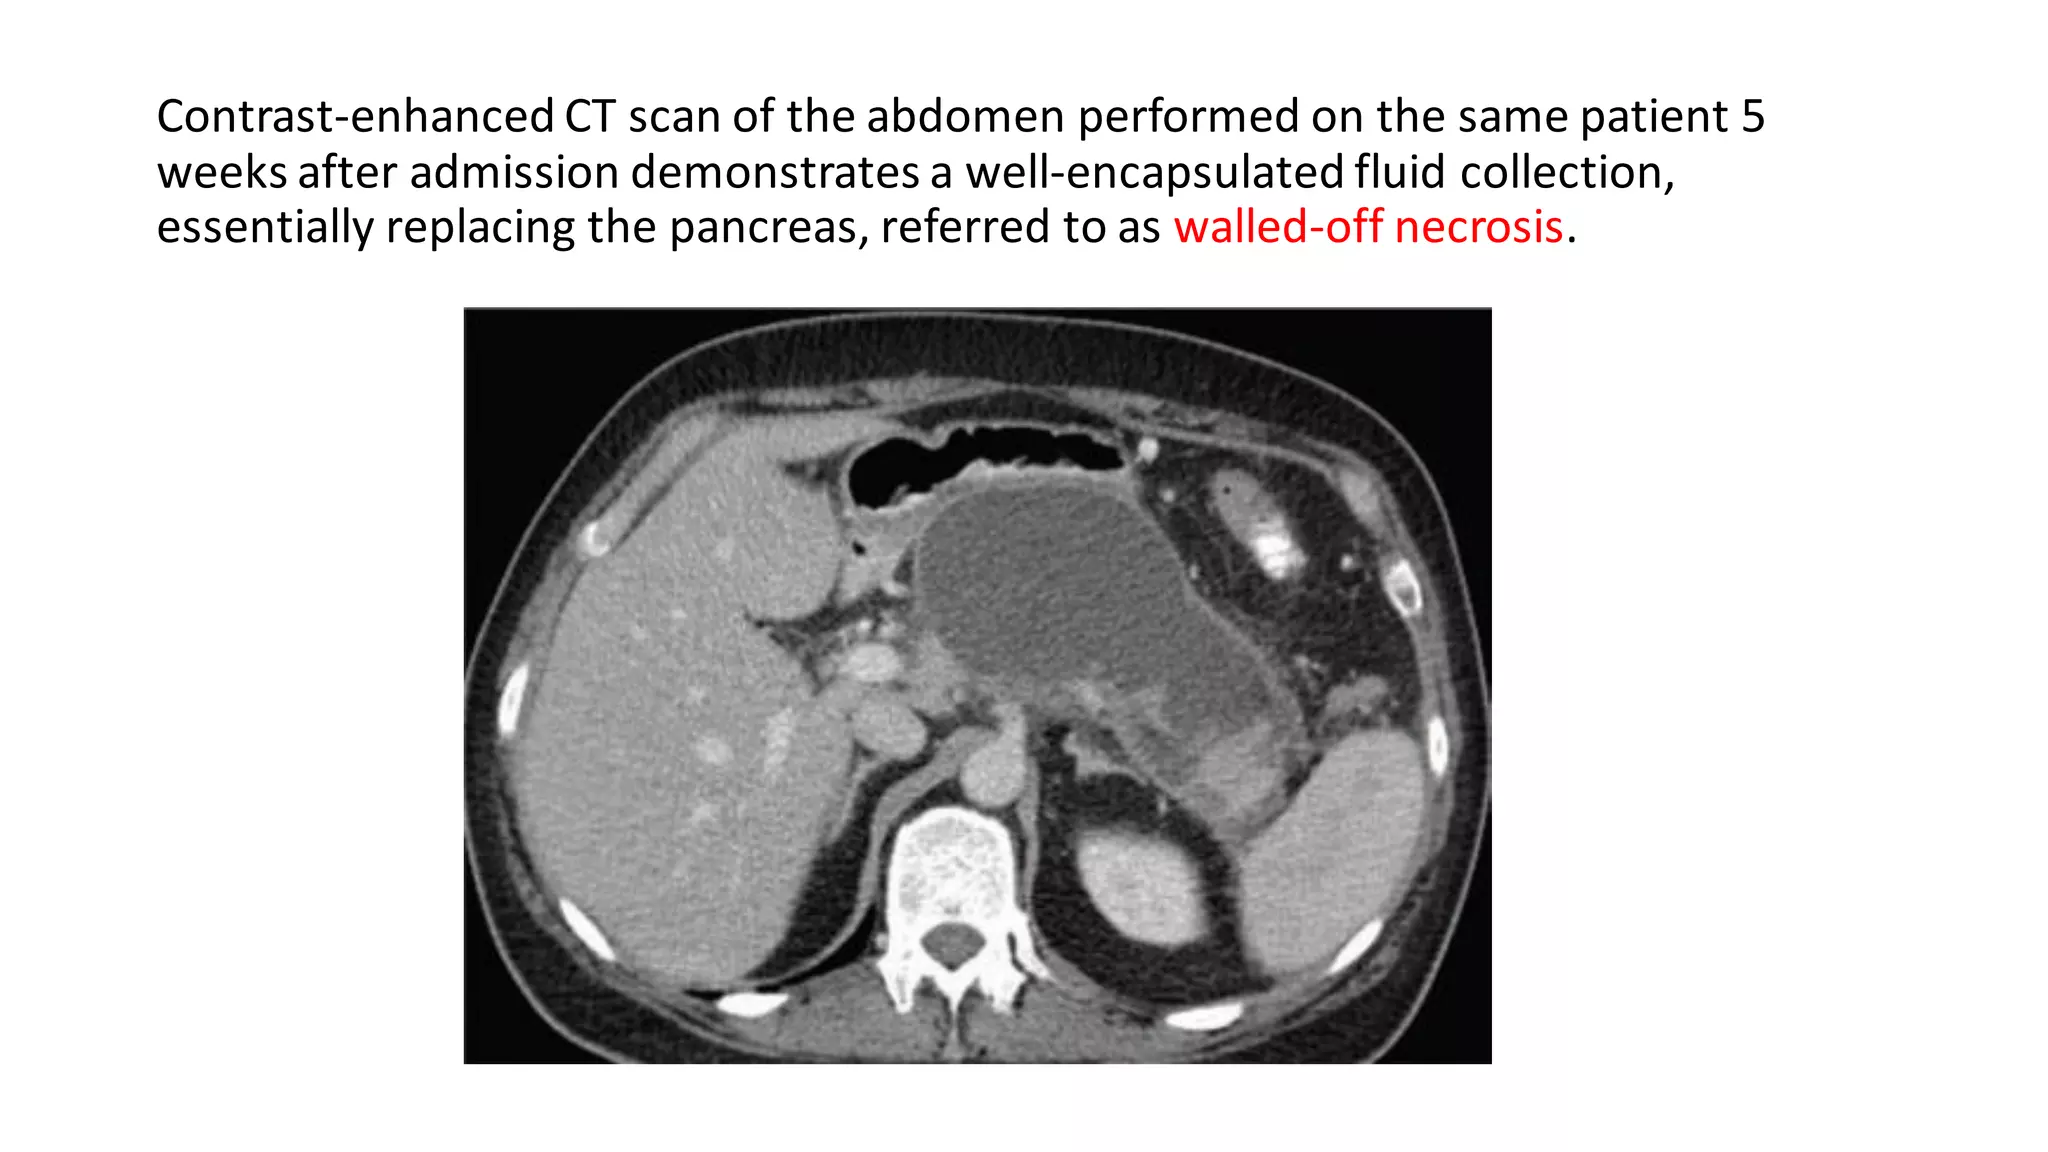

Contrast-enhanced CT scan of the abdomen performed on the same patient 5

weeks after admission demonstrates a well-encapsulated fluid collection,

essentially replacing the pancreas, referred to as walled-off necrosis.

Contrast-enhanced CT scanof the abdomen performed on the same patient 5 weeks after admission demonstrates a well-encapsulated fluid collection, essentially replacing the pancreas, referred to as walled-off necrosis.